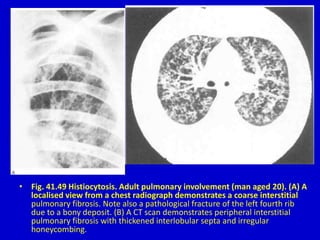

• Fig. 41.49 Histiocytosis. Adult pulmonary involvement (man aged 20). (A) A

localised view from a chest radiograph demonstrates a coarse interstitial

pulmonary fibrosis. Note also a pathological fracture of the left fourth rib

due to a bony deposit. (B) A CT scan demonstrates peripheral interstitial

pulmonary fibrosis with thickened interlobular septa and irregular

honeycombing.

• Fig. 41.49Histiocytosis. Adult pulmonary involvement (man aged 20). (A) A localised view from a chest radiograph demonstrates a coarse interstitial pulmonary fibrosis. Note also a pathological fracture of the left fourth rib due to a bony deposit. (B) A CT scan demonstrates peripheral interstitial pulmonary fibrosis with thickened interlobular septa and irregular honeycombing.